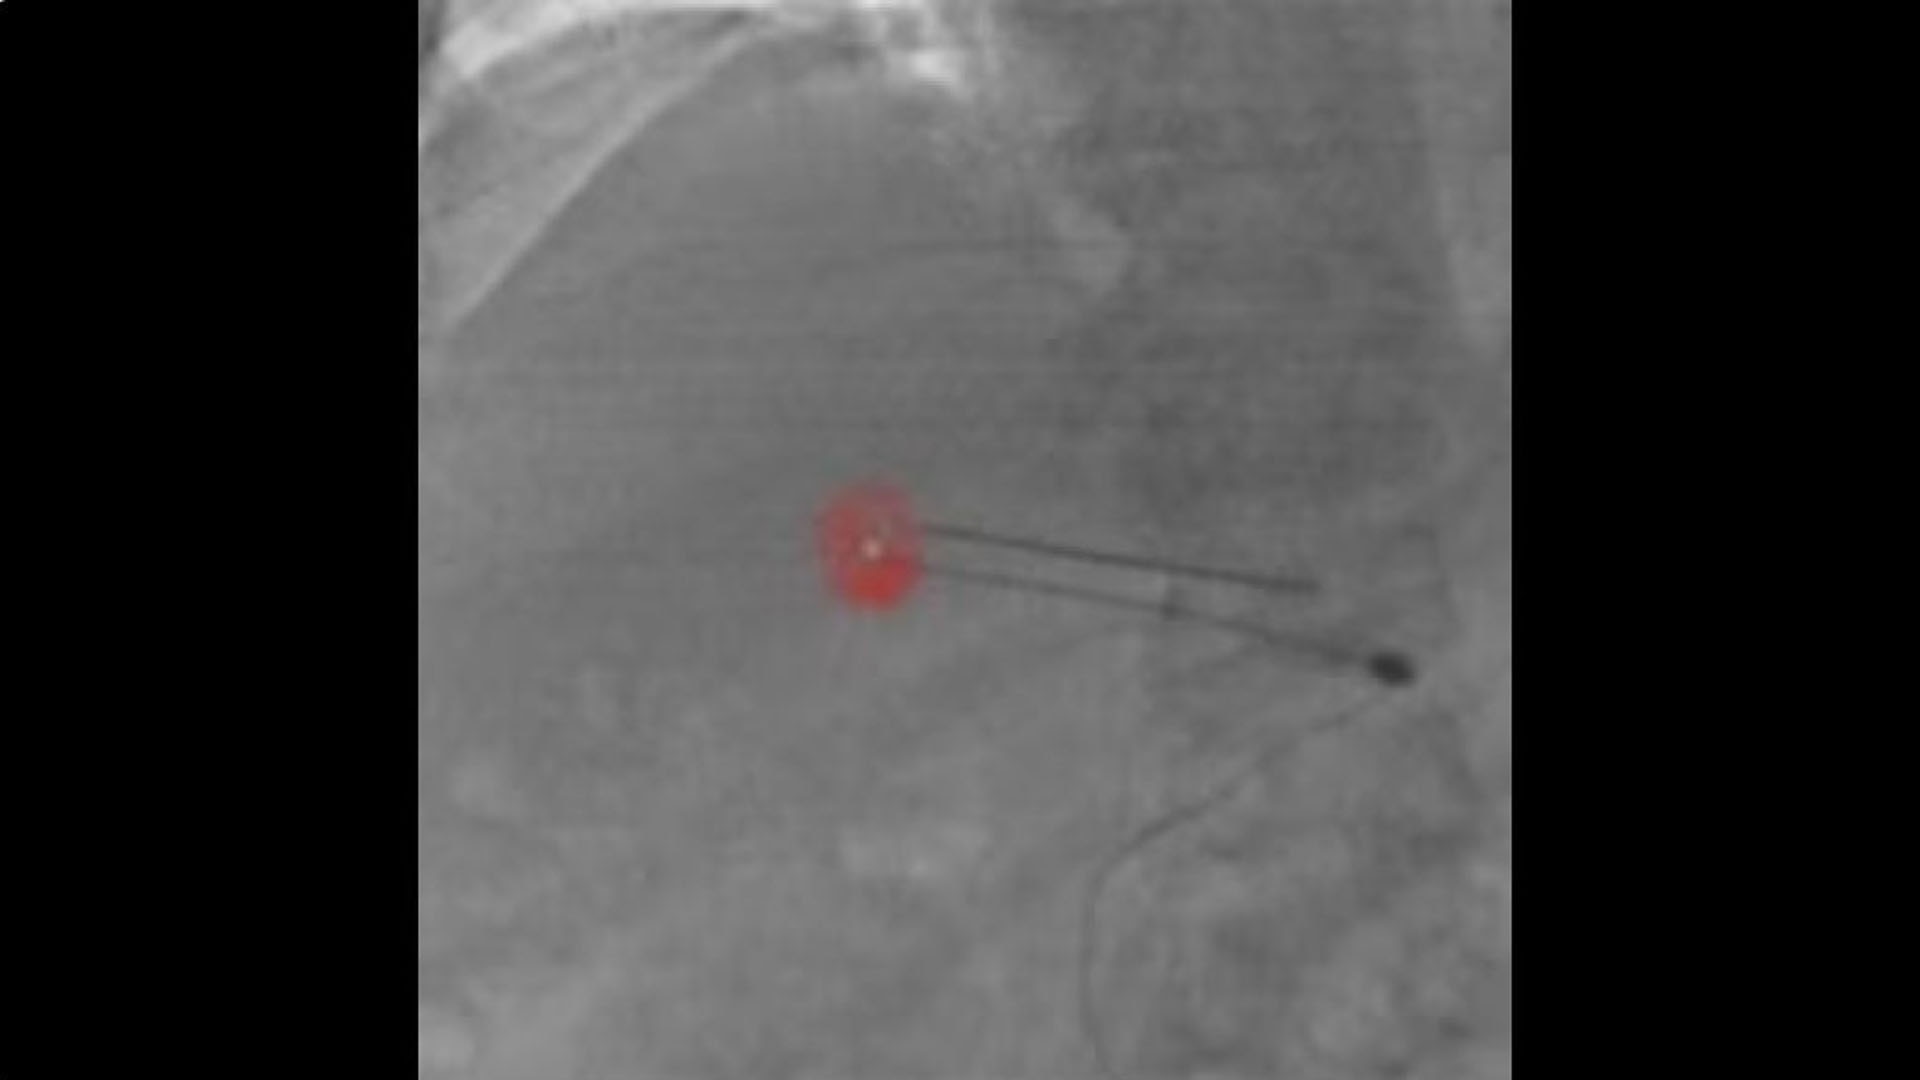

Plan

Define the pathway

Define optimal needle entry points and pathways directly on oblique CBCT cross sections.

hero_sticky_scrolling_1-ci-en